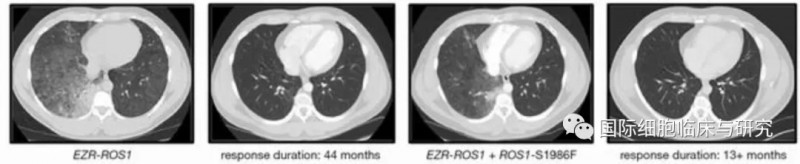

开始他每天接受两次250 mg克唑替尼的一线治疗,持续治疗44个月之后进行了随访,影像显示右下叶原发灶肿大,并伴有新的淋巴管扩散。同时临床症状恶化,咳嗽和不适感增加。

通过肿瘤活检证实为腺癌,无组织学改变。肿瘤基因测序NGS(FoundationOne)显示已知的EZR-ROS1融合基因发生了了ROS1-S1986F抗性突变。此后他开始每天以100 mg的剂量进行二线劳拉替尼治疗。

不到两个月的时间,他就告诉医生呼吸道症状有所改善,且影像学资料证实了肿瘤对劳拉替尼完全响应。

可喜的是,从开始使用劳拉替尼到最近的13个月以来,疾病对治疗持续有反应。